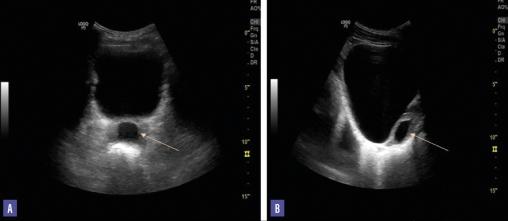

L’échographie sus-pubienne révèle une prostate de taille normale avec présence d’une formation kystique liquidienne anéchogène à paroi régulière mesurant 30 × 20 mm, enchâssée dans le tissu prostatique et se projetant sur la ligne médiane (fig. 1). L’échographie prostatique représente l’élément clé pour le diagnostic du kyste chez ce patient.

L’évolution postopératoire est favorable. Un contrôle réalisé à six mois montre une prostate normale sur l’échographie ainsi qu’une amélioration nette de la numération sur le spermogramme atteignant 20 millions de spermatozoïdes par millilitre de sperme. Le patient a signalé une grossesse survenue spontanément au sein de son couple un an plus tard.

L’échographie prostatique par voie sus-pubienne ou endorectale a un double intérêt diagnostique et thérapeutique, avec la ponction-aspiration du liquide intrakystique. Elle est un examen essentiel pour la classification des kystes prostatiques. En effet, les kystes d’origine müllérienne apparaissent comme une image liquidienne anéchogène à paroi régulière, de topographie médiane intraprostatique. Les kystes des canaux éjaculateurs sont de topographie médiane et légèrement latéralisée et se projettent sur le trajet du canal éjaculateur.4